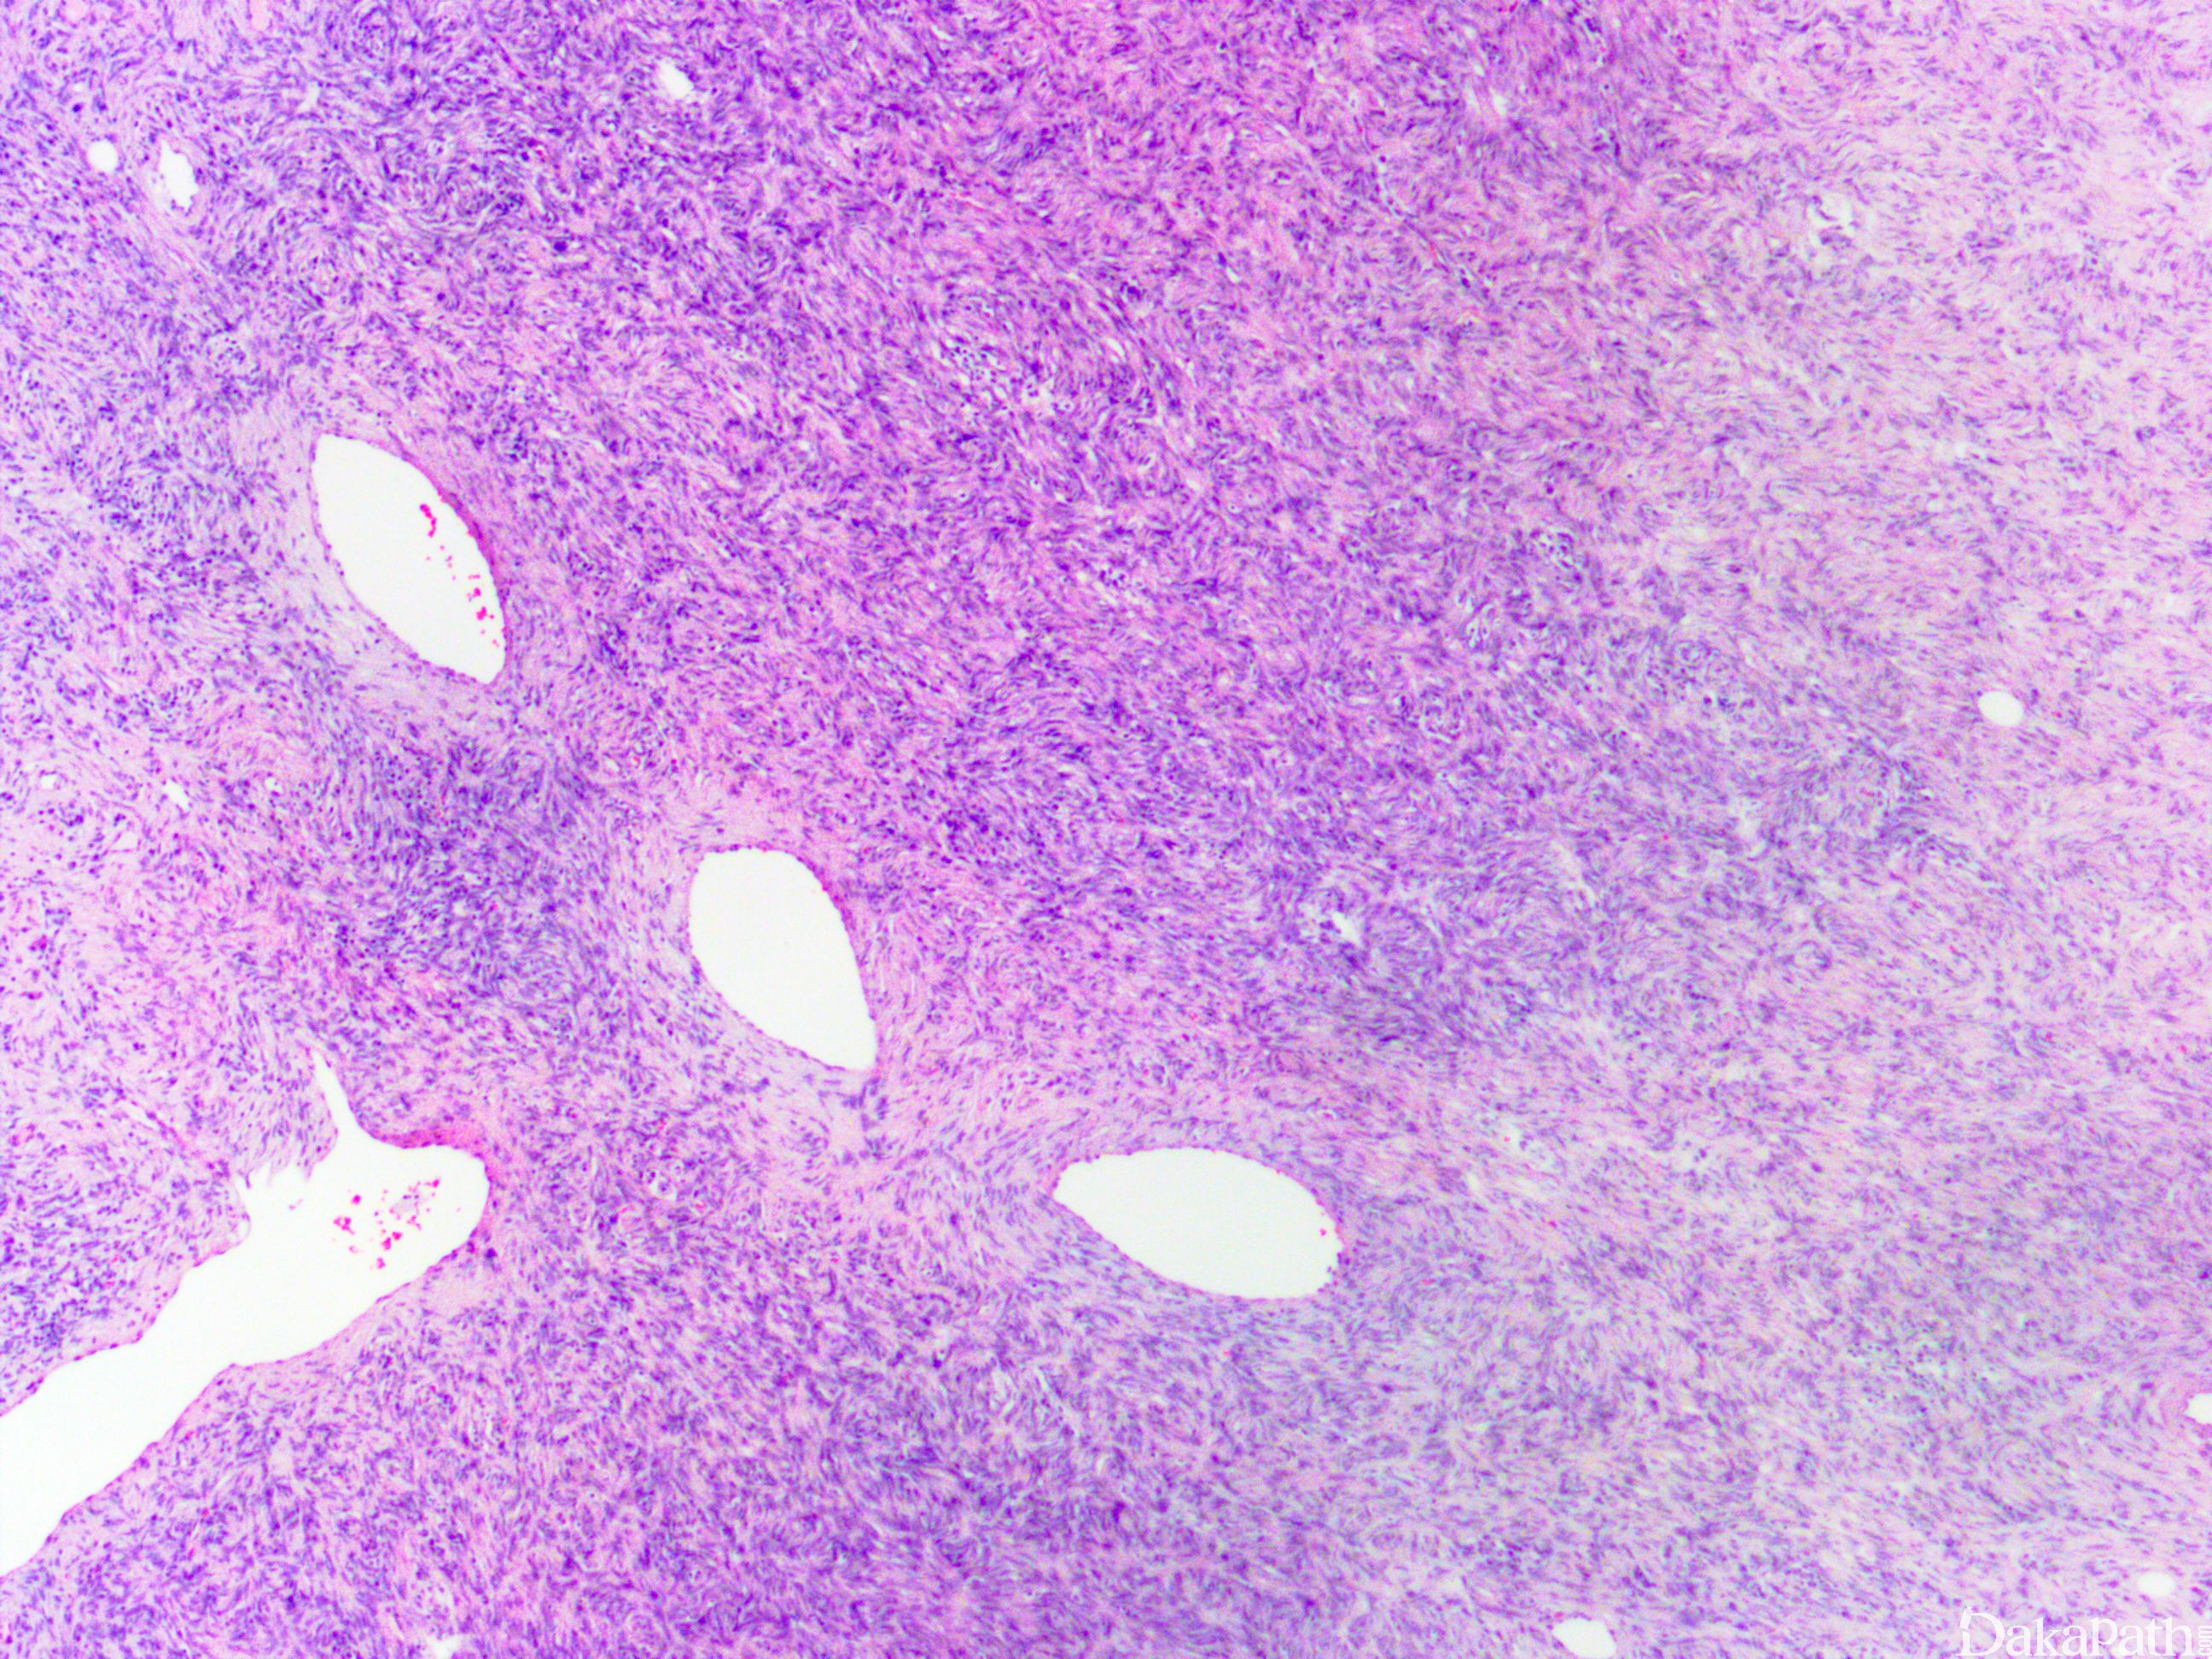

一种发生于皮肤的低度恶性纤维母细胞性肿瘤,组织学上由单型性的梭形细胞呈致密的席纹状结构组成,伴蜂窝状浸润皮下脂肪组织。

肿瘤主要位于真皮层,弥漫浸润性生长,浸润脂肪组织形成特征性的蜂窝状或蕾丝样 (或称花边样)浸润图像;

瘤细胞均匀较一致,呈两端细长的纤维母细胞样,呈一致的致密的席纹状排列,少数病例内可见局灶的血管外皮瘤样排列;

瘤细胞常紧密围绕残留的汗管等皮肤附件组织;